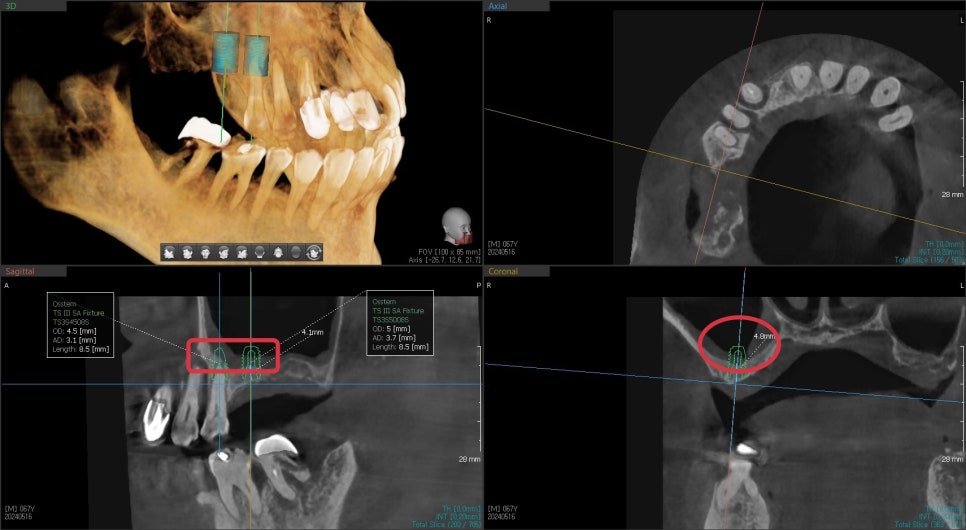

3D CT를 찍은 진단 결과입니다

어금니 쪽의 뼈의 두께가 너무 얇아 임플란트 수술을 위해서는

부비동이라고 알고 있는 상악동 공간에 임플란트 지지 공간을 만들어줘야 합니다.

이것이 상악동 거상술이라는 추가적인 술식이 필요한 이유입니다.

중간쪽 가장 심한 치주염이 진행된 치아 부분입니다.

빨갛게 표시된 부분이 뼈가 있어야 수술이 가능하지만

뼈이식을 동반하더라도 즉시 수술은 불가능한 상태였습니다.